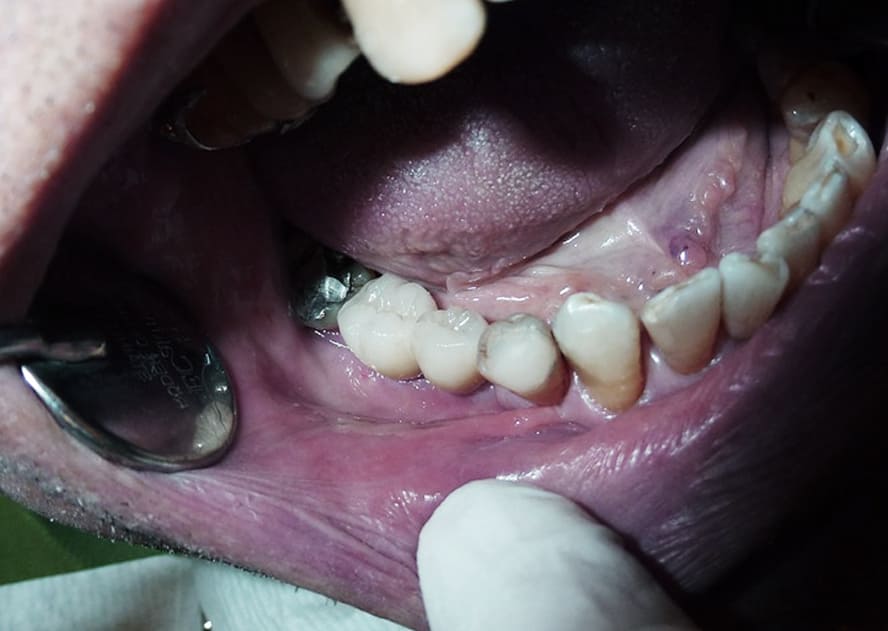

나이가 들면서 치아가 수명은 다하는 것은 당연합니다. 과거에는 빠진 치아를 틀니로 대체하였지만 최근에는 임플란트 시술을 통해 빠진 이를 새로 채웁니다.

앞니 임플란트를 하기 전 임시치아를 하는데 기존 치아와 모양이 굉장히 흡사하고 씹는데는 큰 지장이 없어서 아마 불편함은 없을 것입니다. 또한 임플란트 시술이 보편화되고 고도화됨에 따라 임시치아를 하는 기간이 굉장히 짧아졌으므로 조금 어색함과 이질감이 들더라도 잠깐 동안만 한다고 생각하고 빨리 적응하길 바랍니다.